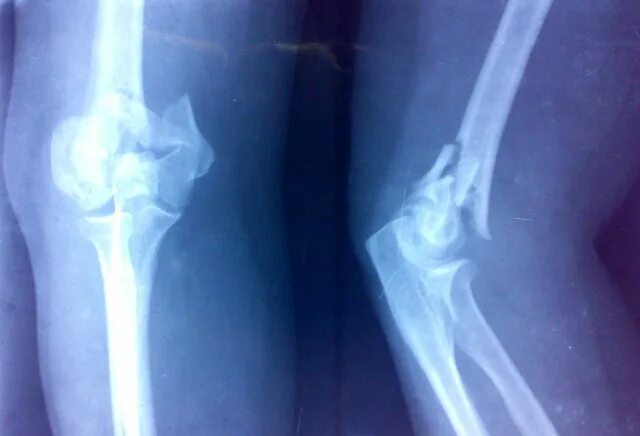

Сколько срастается плечевой перелом